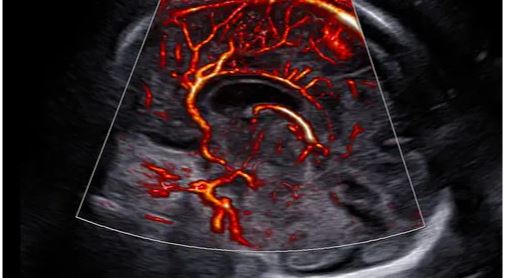

Modes d’imagerie: noir et blanc, doppler couleur, 3D/4D

– CrystalBeam™ est une nouvelle technologie de formation de faisceau bénéfique pour offrir une résolution d’image de haute qualité, et une uniformité accrue des images.

– CrystalLive™ est le moteur d’imagerie échographique Samsung le plus récent, avec un traitement d’image 2D, un rendu 3D et un traitement du signal couleur améliorés, dans lequel on obtient des performances d’image enrichies et un flux de travail efficace pendant les cas complexes.

Une nouvelle formation de faisceau pour une création d’image en profondeur: CrystalBeam™ utilise les technologies Arbitrary Waveform Transmission, Massive Parallel Beamforming et Synthetic Aperture pour produire une fréquence d’images plus rapide et une meilleure uniformité de l’image.